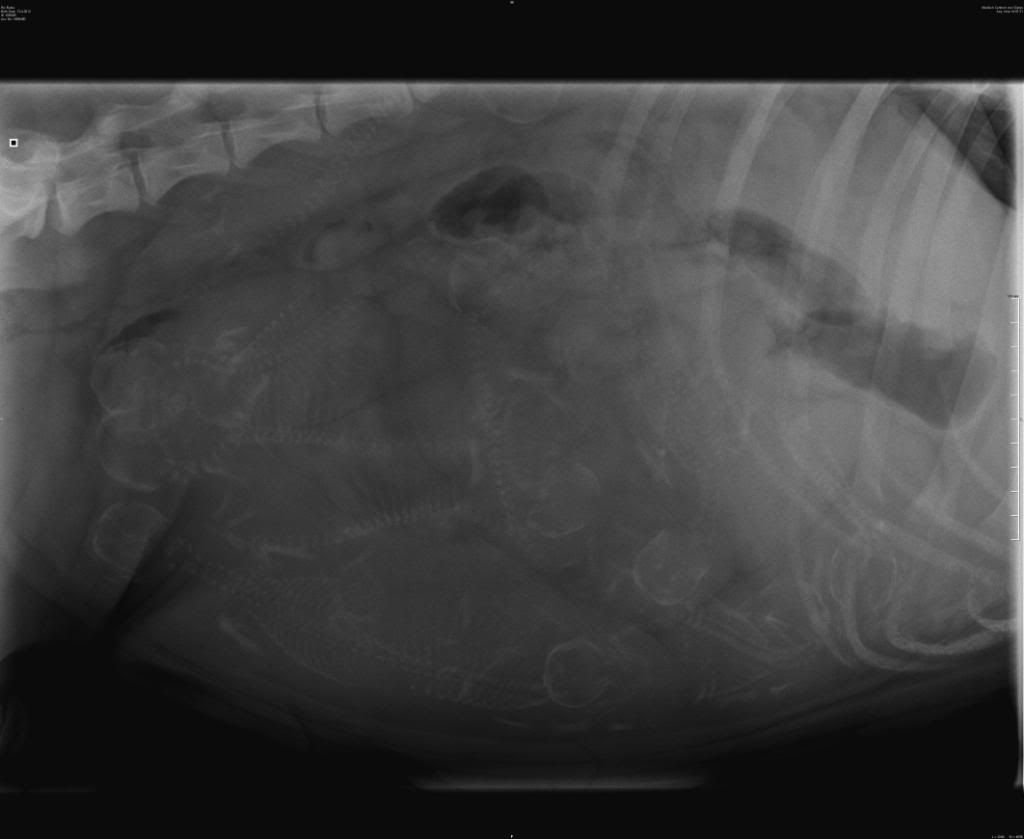

balou zit vandaag op 55 dagen dus de bevalling zit er aan te komen gister rx laten maken dokter zegt 10 ik denk zelf 12 mijn vraag aan jullie hoeveel zien jullie er .

Volgens mij tel ik 12 schedeltjes ... de 11 die aangekruist zijn en bovenin ligt er nog 1.

ik heb de 12 gezien hij zegt dat hij er maar 10 kan tellen vandaar dat ik het hier vraag zet de foto er wel even op zonder de streepjes van mij er ligt er 1 tegen haar ruggengraat aan dat is wat roes al zij .

hierbij een foto van vandaag

Ik denk er ook 12 te zien. Succes met de naderende bevalling!

Ik zie er ook 12 , al twijfel ik eraan of ik een 13e zie of dat t wat anders is.

Ik ga voor 12, maar twijfel ook 12 of 13... Ben benieuwd

Ik zie er toch echt twaalf

Ik tel ook 13 ruggetjes... volle tent daar!

Spannend hoor! Wat een volle buik!!! Ik dacht onder de ribben nog een extra ruggengraadje te zien, maar zie er geen schedeltje bij. Ik tel dus 12 koppies en 13 ruggetjes! Succes!